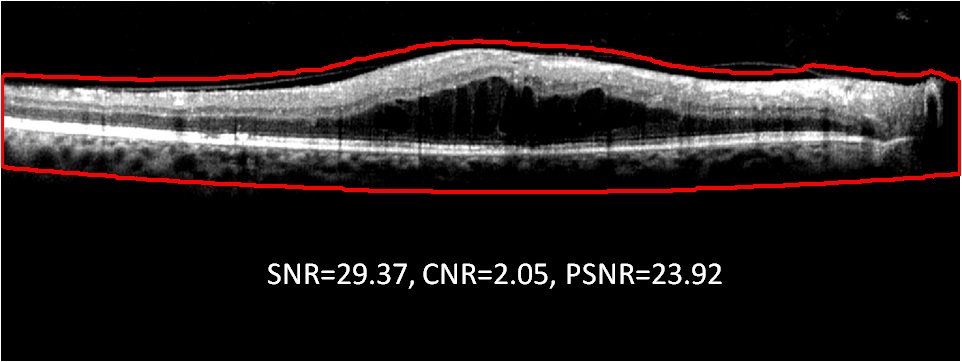

The foreground and background regions for an abnormal OCT image and the denoising performance metrics using the proposed Fourier-domain error based method and the wavelet-based CDWT approach are shown in Fig. 6. Here, we observe that the proposed denoising method retains the surface edges and contrast variation in the foreground region while it significantly reduces image noise from the background region when compared to the denoised image using CDWT.

Refer to caption

Figure 6: Example of automated OCT image denoising. (a) Noisy image (I𝐼I), (b) The foreground region lies within the region bordered by the red boundary. All other regions are the background. (c) Denoised image by CDWT method. (d) Denoised image by the proposed method.

The comparison between denoising metrics using the proposed method and the CDWT method are shown in Table 2. Here, we observe that for OCT images from the normal and abnormal data sets, the proposed denoising method improves the image SNR by 12-13 dB, while the CDWT method improves the SNR by 3-4 dB only. The improvements in CNR fraction by the proposed and CDWT method are about 0.5 and 0.1, respectively. However, the CDWT method achieves PSNR about 4.5 dB greater than the proposed method. The PSNR of the proposed method is smaller than the CDWT method because of the denominator in (1.16) that denotes the similarity in structure between the denoised and noisy image, and a more similar structure will ensure a small value for this quantity. The proposed method alters the structure of the noisy image in the background region due to the underlying Fourier-domain error based Wiener deconvolution strategy, while the CDWT method conserves the image structure, and hence the difference in PSNR. The impact of the gain in SNR by the proposed denoising method versus the gain in PSNR by the CDWT method on automated sub-retinal surface segmentations are analyzed in the next experiments.